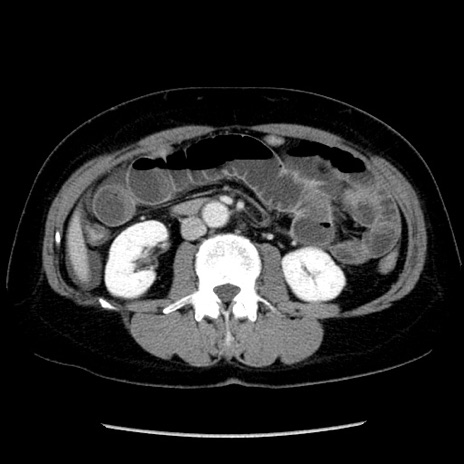

症例6(横断像)

【症例】50歳代女性

【主訴】下腹部痛

【現病歴】本日朝より下痢2回あり。 昼食を食べた後、嘔吐3回、下腹部痛認め、症状軽快せず、当院救急搬送。

【既往歴】卵巣癌術後(8年前に当院で卵巣摘出)

【身体所見】 意識清明、腹部:平坦、腸蠕動音→、やや硬、下腹部自発痛・圧痛あり、反跳痛あり、筋性防御なし。

【データ】WBC 16000、CRP 0.01